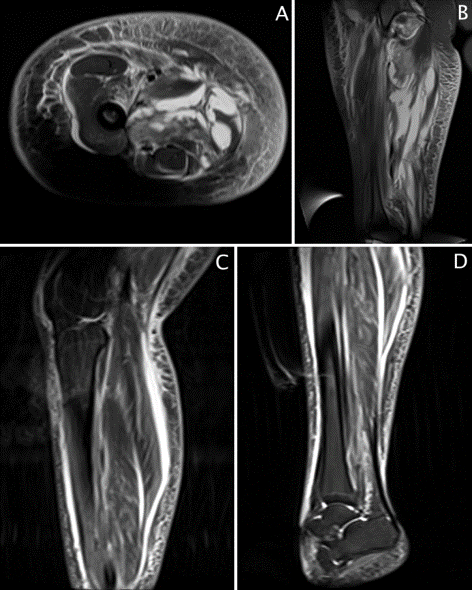

A 16-year-old female was admitted to our children's hospital for intractable right lower extremity pain, edema, fever, elevated white blood count, and elevated serum creatinine kinase. The patient reported a 2-week history of pain that began in the mid abdomen and migrated to the lower extremity. Bedside ultrasound was remarkable for diffuse thigh cellulitis and fluid collections. Emergent magnetic resonance imaging (MRI) was performed demonstrating multi-loculated thigh abscesses, with profound muscle and soft tissue inflammatory changes extending from the femoral canal to the knee (Figure 1A, 1B). In the operating room, a 27-cm medial thigh incision drained 400 cc of foul-smelling purulent drainage from a collection extending from the anterior hip capsule to the knee. Gram stains and culture indicated Escherichia coli (E. coli). There was significant tissue and fascial inflammation with necrosis of the sartorius, pectineus, and adductor magnus, longus, and brevis muscles, necessitating extensive debridement. Following irrigation and debridement, a vacuum assisted wound closure device was placed over the medial thigh. Calf swelling noted during surgery, prompted MRI of the calf demonstrating inflammation and fluid. (Figure 1C, 1D). On hospital day 2, surgery for additional washout yielded additional foul-smelling necrotic tissue from the thigh, necessitating a 37-cm right lateral thigh incision with irrigation and debridement. Lower leg fasciotomy with a 17-cm right lateral incision and a 15-cm medial leg incision exposed all four compartments, with additional purulent drainage. Medial and lateral vacuum assisted wound closure devices were placed on the thigh and leg. Following washout, abdominal and pelvic computed tomography (CT) was obtained to evaluate the abdomen and pelvis. CT showed a dilated appendix with appendicoliths and multiple pelvic abscesses from ruptured appendicitis (Figure 2). Interventional radiology placed a 10 French right lower quadrant drain, obtaining 20 cc of purulent drainage, likewise growing E. coli on culture. Her sepsis progressed, requiring inotropic support with epinephrine and norepinephrine. On day 3, patient was evaluated for appendectomy. She was considered too unstable for laparotomy, therefore, using an extraperitoneal approach, a 10-cm flank incision surgically drained a right iliopsoas abscess. Three separate extraperitoneal Penrose drains (1-inch) were then placed in the retrorenal area, through the femoral triangle, and in the subcutaneous tissue.

Figure 2. CT abdomen and pelvis with contrast. (A) Axial image demonstrates multiple abscesses (*), free fluid(x), inflammatory changes of the subcutaneous and intra abdominal fat and enlarged pelvic appendix (arrow). (B) Coronal image shows dilated appendix with appendicolith (arrow). Postoperative intramuscular air seen (>).

Ruptured appendicitis with contamination of the ipsilateral lower extremity is recognized in cases of retrocecal appendix, primarily affecting older or immunocompromised patients (Table 2). The retrocecal appendix is in close proximity to the psoas, allowing infection from a ruptured appendix to track along tissue planes following the psoas muscle into the thigh as it inserts on the lesser trochanter of the femur.5 A thigh abscess resulting from rupture of a non-retrocecal appendix positioned in the right pelvis (Figure 2), as in this case, is unreported in the literature.6 Furthermore, ruptured appendiceal abscess tracking along the femoral vessel all the way to the foot is unreported.